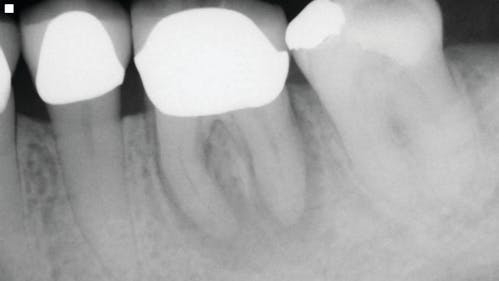

Periapical Lesions Does The Size Of An Endodontic Lesion Play A Role In Success And Failure Dental Economics

A Concise Guide To Pathology Within Endodontics American Association Of Endodontists